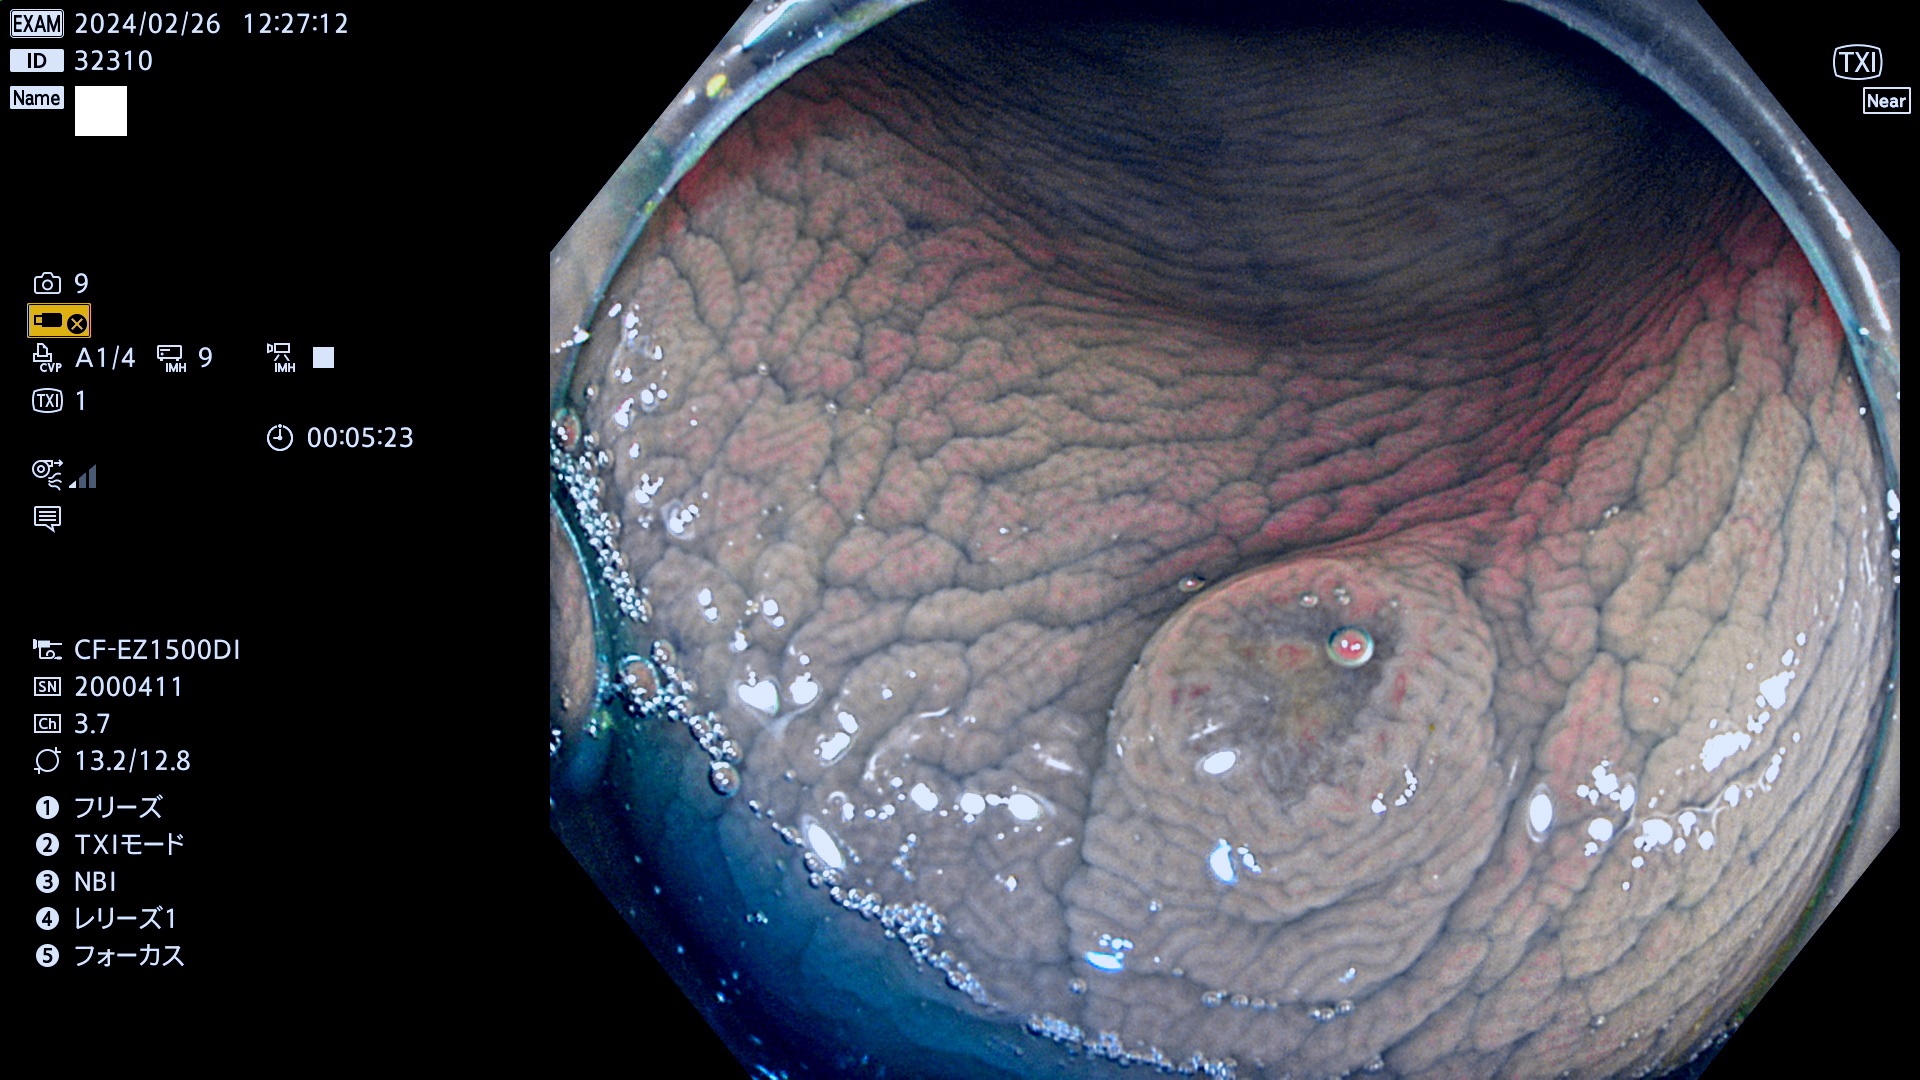

表面型腺腫(Flat Adenoma)の中で、完全に平坦な物をUb、陥凹している物をUcと呼びます。平坦隆起型(Ua)よりも、発見が難しく危険な病変です。

専門的)何故、陥凹していると危険? 癌遺伝子の変異が蓄積すると細胞分裂が盛んになり隆起するのでは?と通常は思われるでしょう。しかし実際は逆です。これは2022年の記事にある「細胞はストレスに直面したら細胞分裂を止める(細胞老化に入り休眠する)という生命の基本的現象」によるものです(Oncogene Stress)。細胞老化を起こすのが癌抑制遺伝子で、この安全装置(ブレーキ)が壊れると癌になります(休眠からの覚醒)。ですから陥凹は「まだ癌では無いが癌化の直前」を意味します。特に「小サイズなのに陥凹している」病変は短期間に腫瘍進化(⇒2021年記事)が起きたことを意味します(=ゲノム不安定性

専門的)Uc=De Novo癌? 内視鏡の解像度が低かった時代、このような説もありました。しかし今日の高精度内視鏡では良性の微小なUc型腺腫が日常的に見つかります。私見ですが「Ucこそが多段階発癌(Adenoma-Carcinoma Sequence)のMain Route」と考えます。

毎週の検査(木・金・土・日)に発見されたUb、Uc型・腺腫を、その週の日曜の夜にUPし1週間、提示します。

抽出の対象期間 2024年2月22日(木)〜2月25(日)の5日間(50件の検査)5件 (5/50=10%)